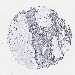

PANCREATIC CANCER - Protein expressioni

A mouse-over function shows sample information and annotation data. Click on an image to view it in a full screen mode. Samples can be filtered based on level of antibody staining by selecting one or several of the following categories: high, medium, low and not detected. The assay and annotation is described here.

Note that samples used for immunohistochemistry by the Human Protein Atlas do not correspond to samples in the TCGA dataset.

Antibody stainingi

Antibody staining in the annotated cell types in the current human tissue is reported as not detected, low, medium, or high, based on conventional immunohistochemistry profiling in selected tissues. This score is based on the combination of the staining intensity and fraction of stained cells.

Each image is clickable and will lead to virtual microscopy that enables deeper exploration of all samples and also displays staining intensity scores, fraction scores and subcellular localization as well as patient and tissue information for each sample.

Antibody HPA021302

Antibody HPA021311

Antibody HPA021479

Adenocarcinoma, NOS